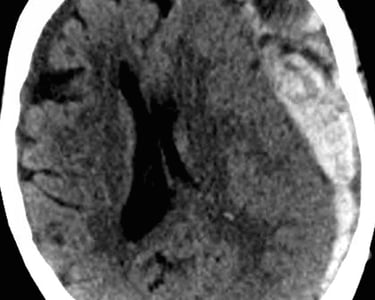

Hemorragias cerebrales

Aneurismas cerebrales